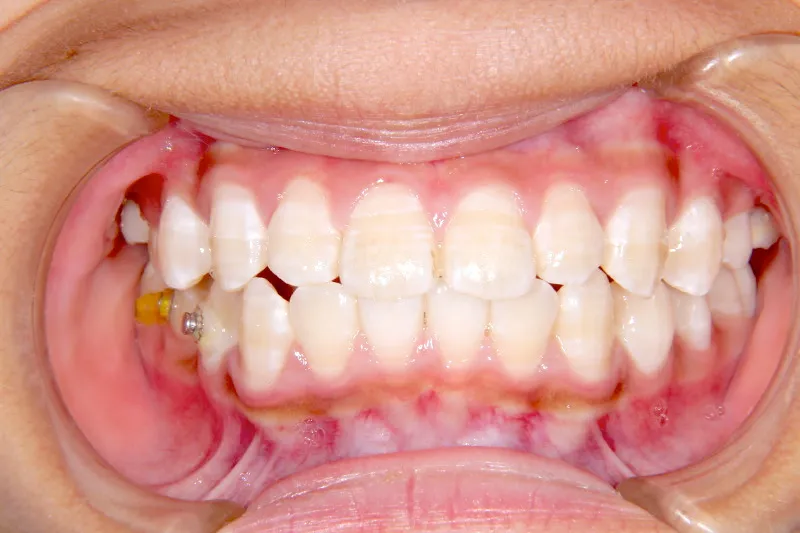

【子供の矯正(一期)】叢生・開咬・前歯で噛めない・舌癖・7歳女児【M.O様】

治療終了後

治療回数31回、4年11ヶ月の治療期間で矯正治療を終了しました。

主訴が改善され、ご満足頂きました。